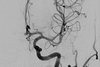

Identificação humana

Desastres de massa